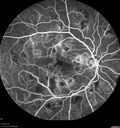

61 year old man - he had chemotherapy for his hairy cell leukemia in the middle of August. He started having trouble with light sensitivity after his diagnosis and he started seeing spots. Right now he feels like he is looking through a grid. He has a friend who is a pediatric hematologist up north. There was some concern that he might have retinal hemorrhages associated with the Leukemia. His white count was over 100,000. Now his white is low. His platelets are back to normal. His red count is also low. •VA OD: sc20/32 PHNI •VA OS: sc20/25-2 The images show extensive non-perfusion. The right eye developed proliferation and required PRP about 3 months after these photos were taken.